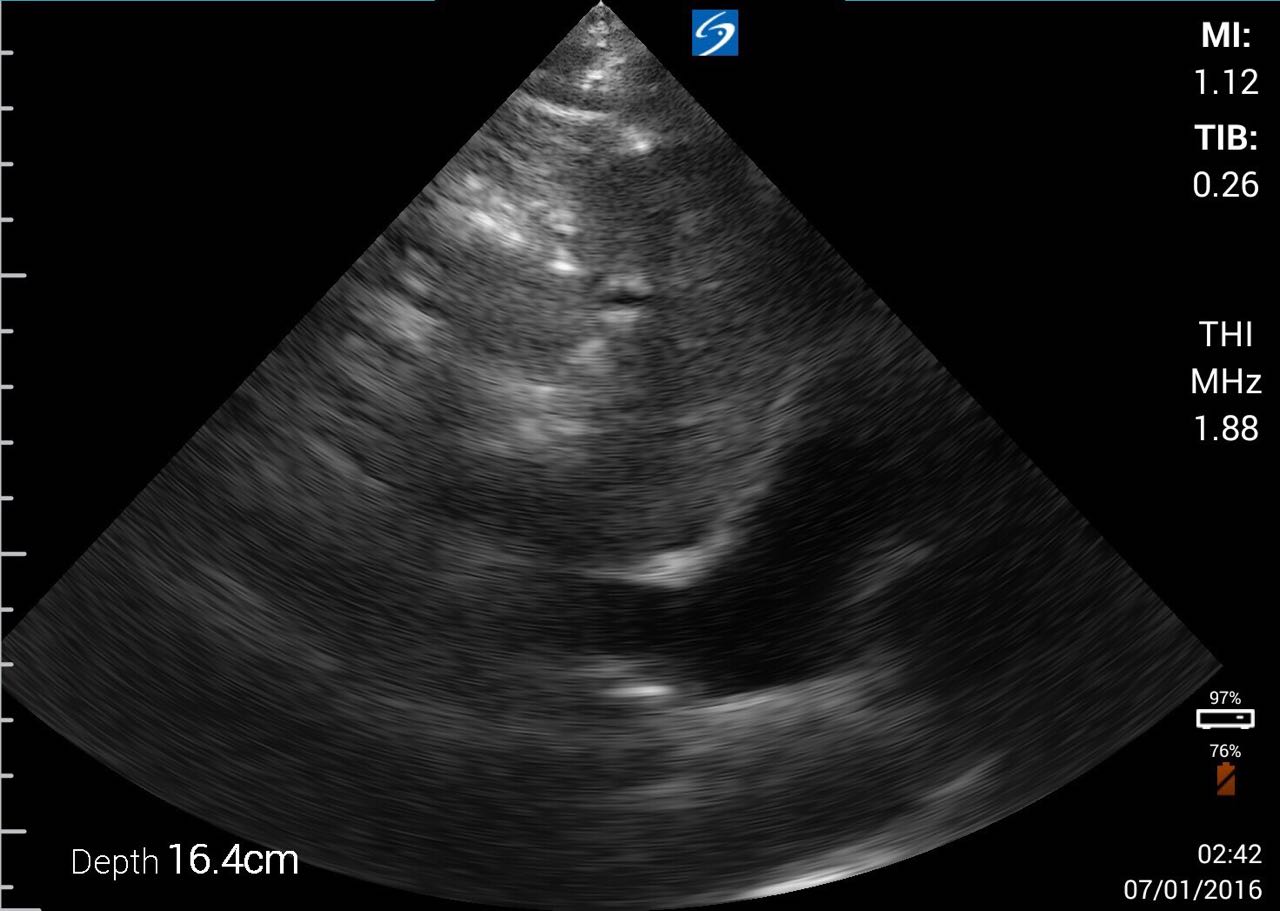

下載的影片: IVC (錄影的秒數可以自定)